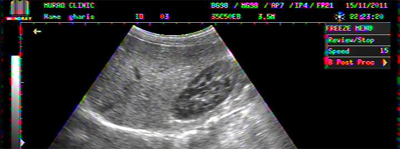

BILATERAL PLEURAL EFFUSION IN A 03 YEARS OLD BOY WITH DHF

BILATERAL PLEURAL EFFUSION COMPLETELY REABSORBED AFTER 3 WEEKS